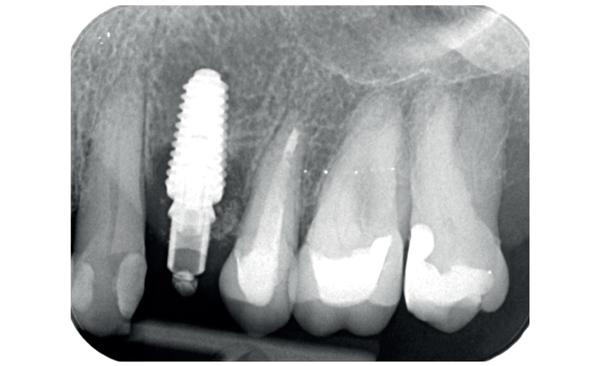

De implantaatplaatsing en de beslissende fout (afbeelding 1-13)

De extractie verliep voorspoedig, waarbij ik zoals al-

primaire stabiliteit van 60 Ncm.

11. Röntgenfoto ter controle van de plaatsing en de angulaire. Dit bone-level implantaat werd 4 mm onder de weke delen geplaatst.

12. Direct post-op. Een direct geplaatste tijdelijke kroon. Vastgezet met een torque van 20 Ncm en gehecht met prolene 5/0.

tijd probeerde de buccale botlamel intact te houden. Dit is cruciaal voor latere botbehoud en implantaatplaatsing. Na curettage en spoelen van de alveole beoordeelde ik de situatie opnieuw: de botcondities leken gunstig voor een immediaat implantaat.

Hier begon echter de cruciale fout in mijn klinisch besluitvormingsproces. In mijn streven naar maximale primaire stabiliteit - wetende dat immediaat belasten enkel mogelijk is bij hoge stabiliteit -on-

13. Röntgenfoto ter controle van de pasvorm van de direct geplaatste tijdelijke kroon.

derprepareerde ik de osteotomie. Dit betekende dat ik een iets te smal implantaatbed creëerde, in de hoop dat het implantaat stevig in het bot verankerd zou worden.

Op papier leek dit een logische stap: het MegaGen AnyRidge-implantaat dat ik koos, gaf me een stabiliteit van 60Ncm—een cijfer dat vertrouwen gaf in immediaat belasten. Maar in mijn enthousiasme had ik onvoldoende rekening gehouden met de biologische gevolgen van overmatige compressie.